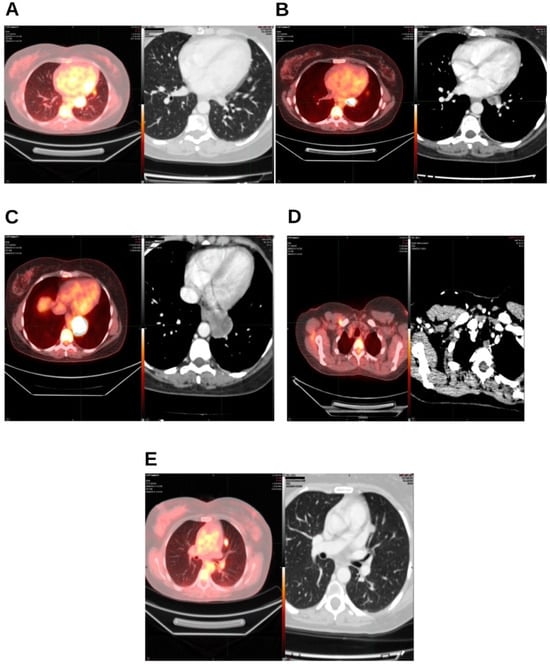

Integrative Use of Cannabidiol, Melatonin, and Oxygen–Ozone Therapy in Triple-Negative Breast Cancer with Lung and Mediastinal Metastases. A Case Report

Background and Clinical Significance: Breast cancer is the most frequent malignancy in women. Metastatic breast cancer is considered a treatable but incurable condition, with a median overall survival of only 2–3 years. Among its subtypes, triple-negative breast cancer (TNBC) accounts for a high proportion of breast cancer-related deaths. It is characterized by an aggressive clinical course, early recurrence, and a strong propensity for visceral and brain metastases. Case Presentation: We report the case of a Caucasian woman who developed systemic disease recurrence with lung and mediastinal lymph node metastases, occurring two years after her primary diagnosis and treatment for TNBC. The patient received three months of chemotherapy combined with an adjuvant integrative protocol consisting of melatonin, cannabidiol, and oxygen–ozone therapy. This combined approach led to the complete disappearance of the lung nodules. Subsequently, stereotactic radiotherapy was performed and, in association with the ongoing integrative treatment, resulted in a significant reduction in mediastinal adenopathy. Introduction of immunotherapy, supported continuously by the same adjuvant strategy, achieved a complete and durable remission. Strikingly, the patient remained disease-free five years after the diagnosis of lung and mediastinal metastases. Conclusions: This clinical case highlights the potential benefit of using melatonin, cannabidiol, and oxygen–ozone therapy as part of an integrative approach in patients with aggressive metastatic TNBC. While it is not possible to establish causality from a single case, the sustained remission observed suggests that such unconventional adjuvant strategies could play a supportive role in enhancing the efficacy of standard oncologic therapies. Full article

Figure 1